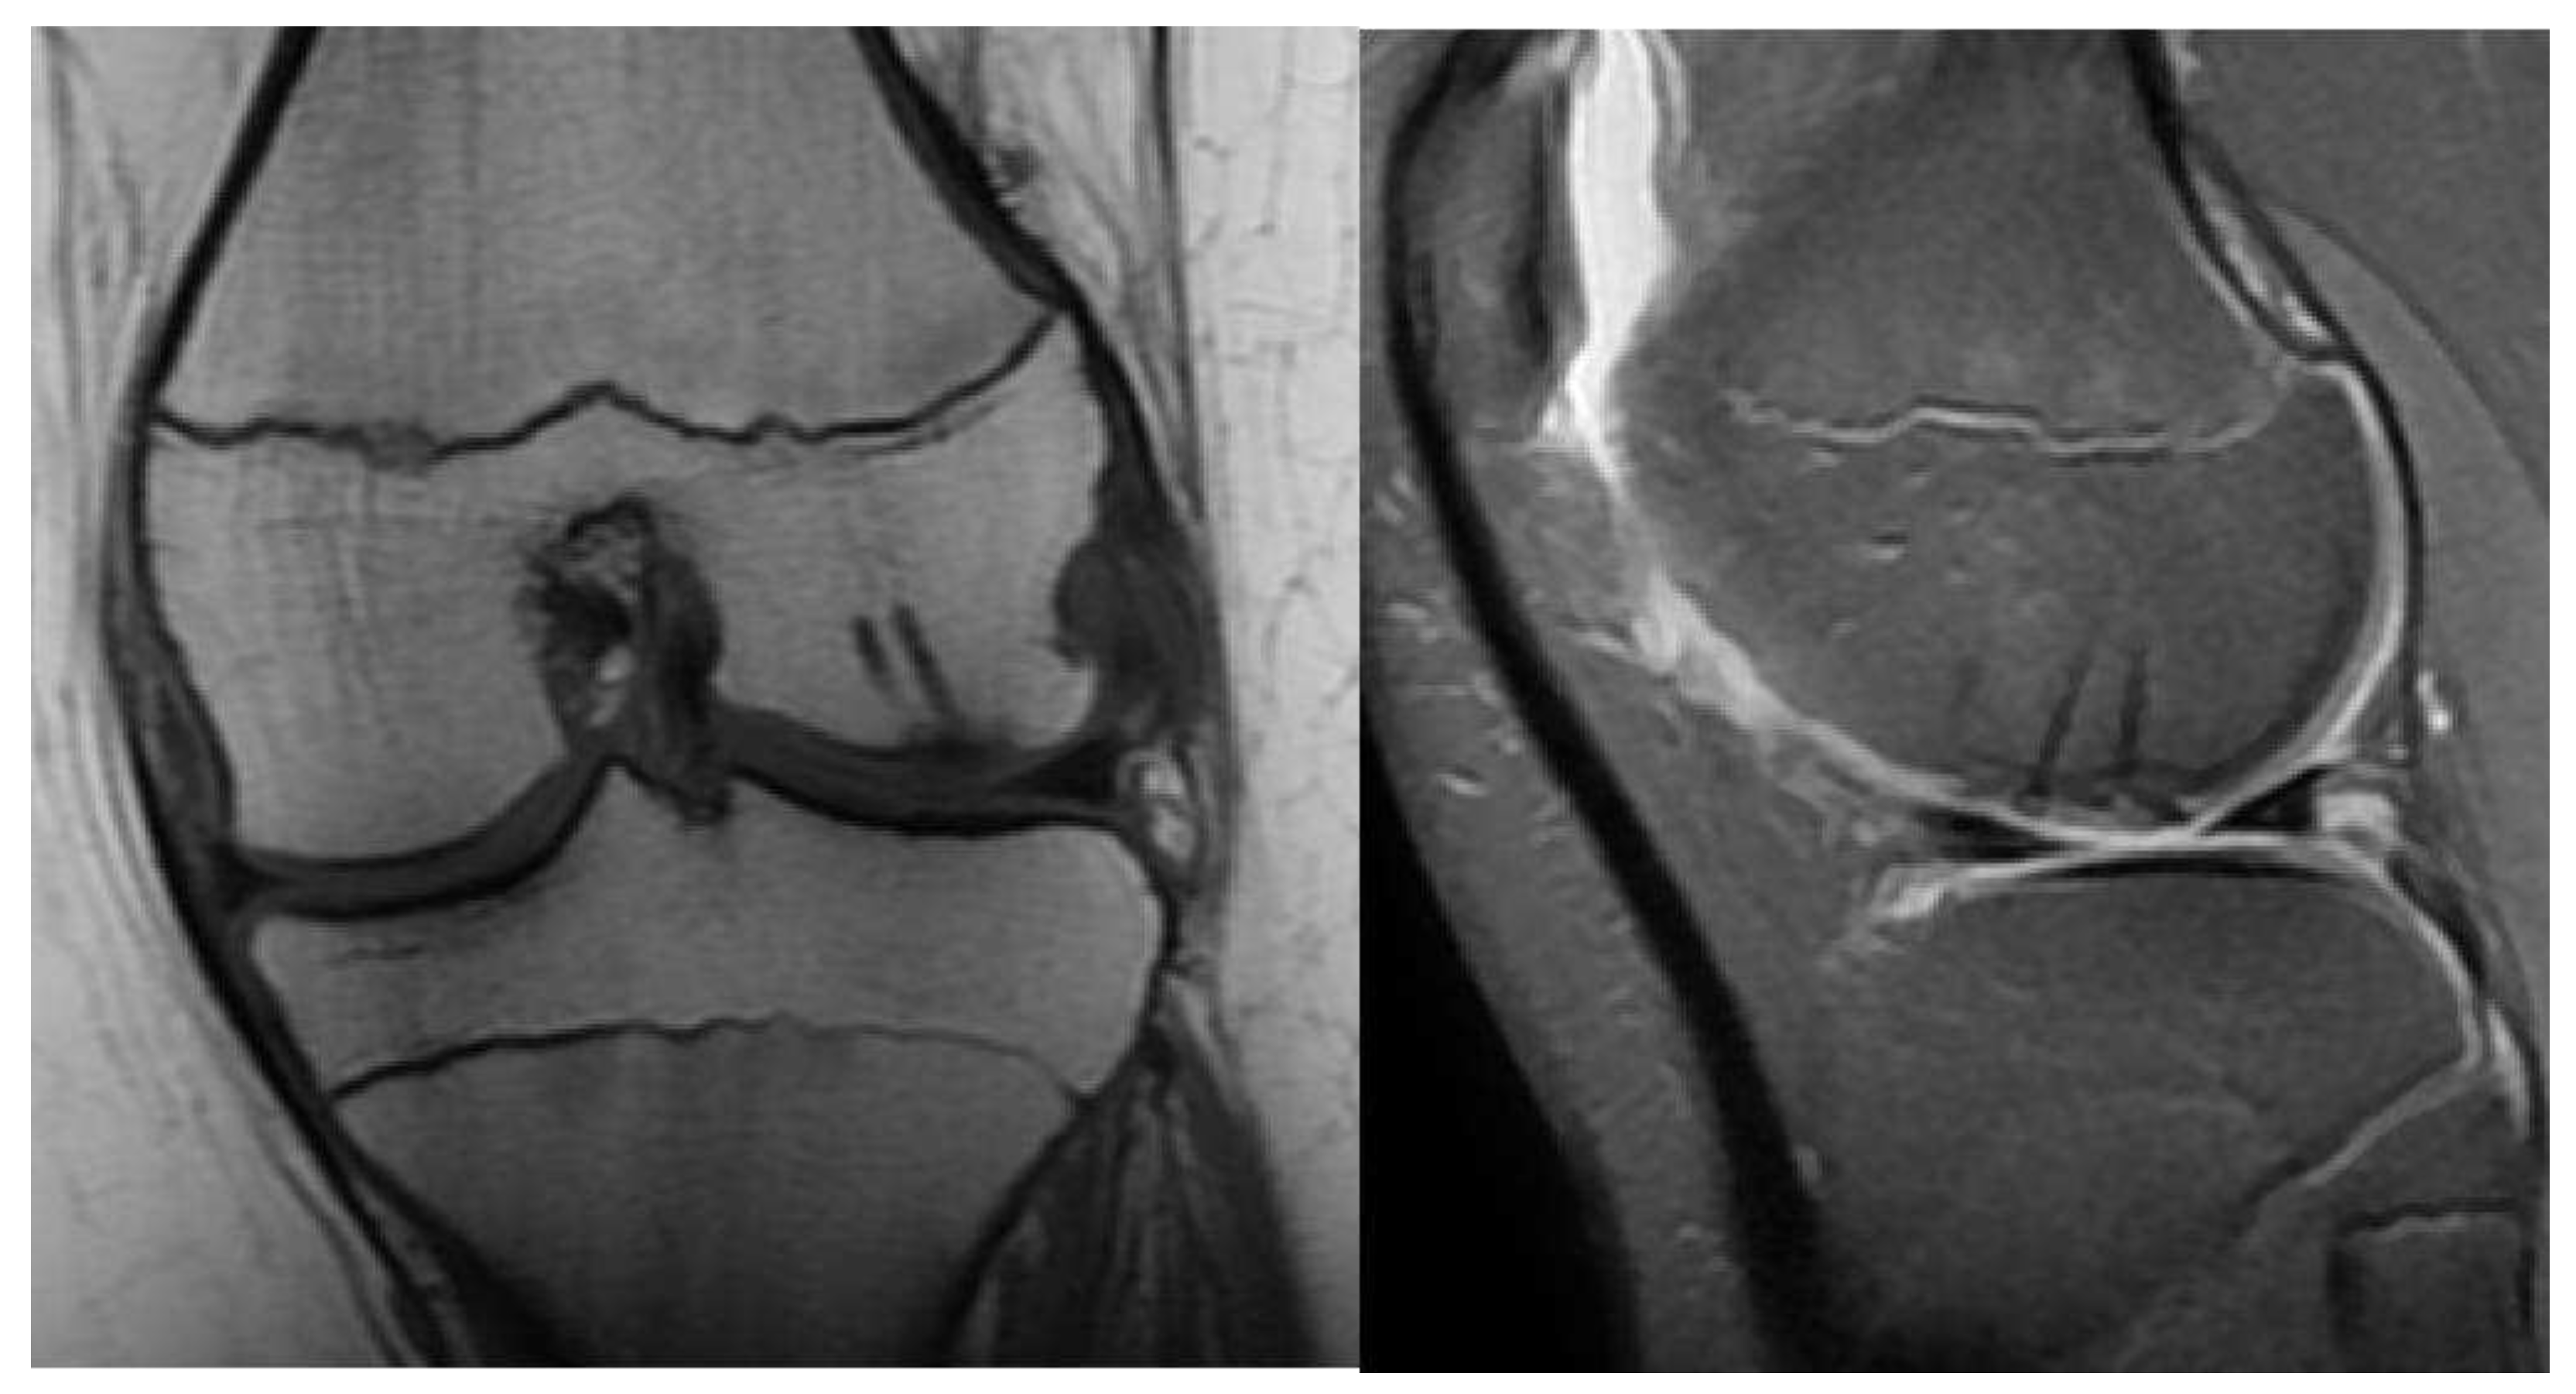

- Type A: Cystic on CT and Edema on MRI

- Type B: Non-displaced and incompletely undercut by fluid (MRI) and lucency (CT) with an open connection to the articular cartilage.

- MRI: Rim-sign - high signal around fragment